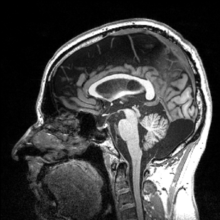

More recently, computed tomography has played a large role in reconstructing endocasts. The procedure is non-invasive and has the advantage of being able to analyze a fossil in record time with little risk of damaging the fossil under review. CT imaging is achieved through the application of x-rays to produce tomographs, or sectional density images, which are similar to the images produced during MRI scans.[8] CT scans use slices approximately 1 mm thick to reconstruct a virtual model of the specimen.[9] This method is especially useful when a fossil cranium is occupied by a natural endocast that cannot be removed without destroying the skeletal portions of the fossil. Because the cranium and its contents are of different densities, the endocranial cavity and its unique traits can be reconstructed virtually.[8]

Recent studies by Emiliano Bruner, Manuel Martin-Loechesb, Miguel Burgaletac, and Roberto Colomc have investigated the connection between midsagittal brain shape and mental speed. This study incorporated human subjects' cognitive testing in relationship to extinct humans. They used 2D from 102 MRI-scanned young adult human for comparison. Such correlations are small, suggesting that the influence of midsagittal brain geometry on individual cognitive performance is negligible but still provides useful information of evolutionary traits of the brain. Areas associated with the parietal cortex appear to be involved in relationships between brain geometry and mental speed.[18]